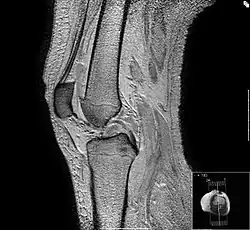

- L'antenne genou : il s'agit d'une antenne émettrice-réceptrice ou réceptrice simple. Il s'agit d'une antenne modulaire de 22 cm de diamètre (peut varier). Elle est adaptée à l'exploration du genou, mais aussi du pied et de la cheville.

- les articulations et les structures adjacentes (hanches, genoux, ménisques, ligaments croisés, tendon, os), notamment chez les sportifs ;